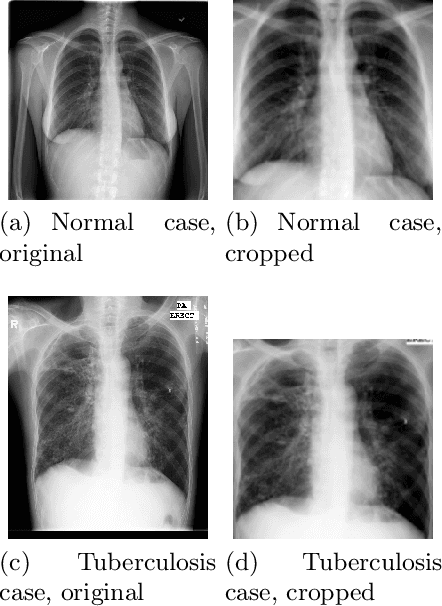

Abstract:Tuberculosis remains a critical global health issue, particularly in resource-limited and remote areas. Early detection is vital for treatment, yet the lack of skilled radiologists underscores the need for artificial intelligence (AI)-driven screening tools. Developing reliable AI models is challenging due to the necessity for large, high-quality datasets, which are costly to obtain. To tackle this, we propose a teacher--student framework which enhances both disease and symptom detection on chest X-rays by integrating two supervised heads and a self-supervised head. Our model achieves an accuracy of 98.85% for distinguishing between COVID-19, tuberculosis, and normal cases, and a macro-F1 score of 90.09% for multilabel symptom detection, significantly outperforming baselines. The explainability assessments also show the model bases its predictions on relevant anatomical features, demonstrating promise for deployment in clinical screening and triage settings.

Abstract:Tuberculosis persists as a global health crisis, especially in resource-limited populations and remote regions, with more than 10 million individuals newly infected annually. It stands as a stark symbol of inequity in public health. Tuberculosis impacts roughly a quarter of the global populace, with the majority of cases concentrated in eight countries, accounting for two-thirds of all tuberculosis infections. Although a severe ailment, tuberculosis is both curable and manageable. However, early detection and screening of at-risk populations are imperative. Chest x-ray stands as the predominant imaging technique utilized in tuberculosis screening efforts. However, x-ray screening necessitates skilled radiologists, a resource often scarce, particularly in remote regions with limited resources. Consequently, there is a pressing need for artificial intelligence (AI)-powered systems to support clinicians and healthcare providers in swift screening. However, training a reliable AI model necessitates large-scale high-quality data, which can be difficult and costly to acquire. Inspired by these challenges, in this work, we introduce an explainable self-supervised self-train learning network tailored for tuberculosis case screening. The network achieves an outstanding overall accuracy of 98.14% and demonstrates high recall and precision rates of 95.72% and 99.44%, respectively, in identifying tuberculosis cases, effectively capturing clinically significant features.